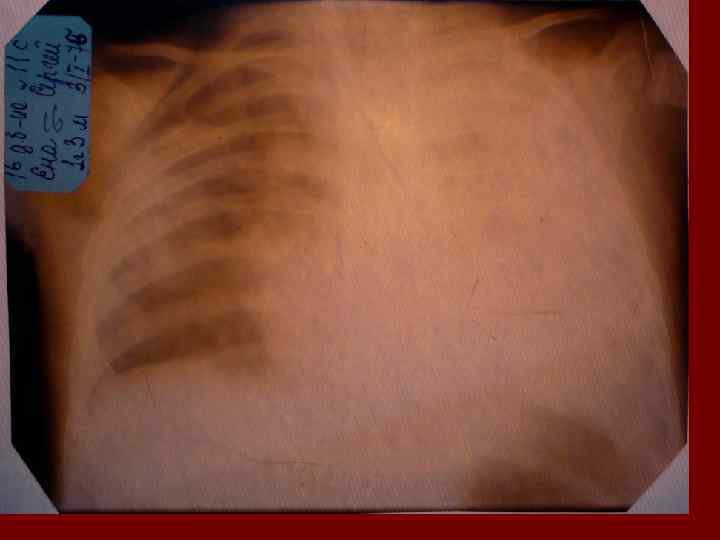

Долевая пневмония характеризуется лобарным пневмоническим инфильтратом. Крупозная ( пневмококковая) пневмония диагностируется прежде всего по клиническим данным. Крупозная пневмония сохраняет свою типичную картину пневмококковой пневмонии: острое начало с характерными клиническими данными, циклическое течение, несклонность к деструкции, гомогенной и лобарной инфильтративной тенью при рентгенологическом исследовании. Вместе с тем, широкое использование антибиотиков способствовало значительному снижению числа крупозных пневмоний у детей. Интерстициальная – редкая форма пневмоний, при которой оказывается поражен прежде всего интерстиций. Как правило, интерстициальная пневмония обусловлена вирусами, пневмоцистами, внутриклеточными микроорганизмами и грибами.

Морфологическую форму пневмонии определяют по клинико – рентгенологическим данным: выделяют очаговую, очагово – сливную, долевую ( крупозную), сегментарную и интерстициальную пневмонии. Очаговая – наиболее распространенная форма. Пневмонические очаги чаще бывают размером 1 см и более. Очагово – сливная – инфильтративные изменения в нескольких сегментах или во всей доле легкого, на фоне которых могут быть видны более плотные участки инфильтрации и/или полости деструкции. Сегментарная – в процесс вовлекается весь сегмент, который, как правило, находится в состоянии гиповентиляции, ателектаза. Морфологическая картина воспаления при очаговых и сегментарных пневмониях связана с первичным инфекционным воспалением в бронхах, что дает основание отнести эти варианты поражения легочной ткани к бронхопневмониям, нередко сопровождающихся бронхообструктивным или бронхообтурационным синдромами. В настоящее время данный тип пневмоний у детей встречается наиболее часто.